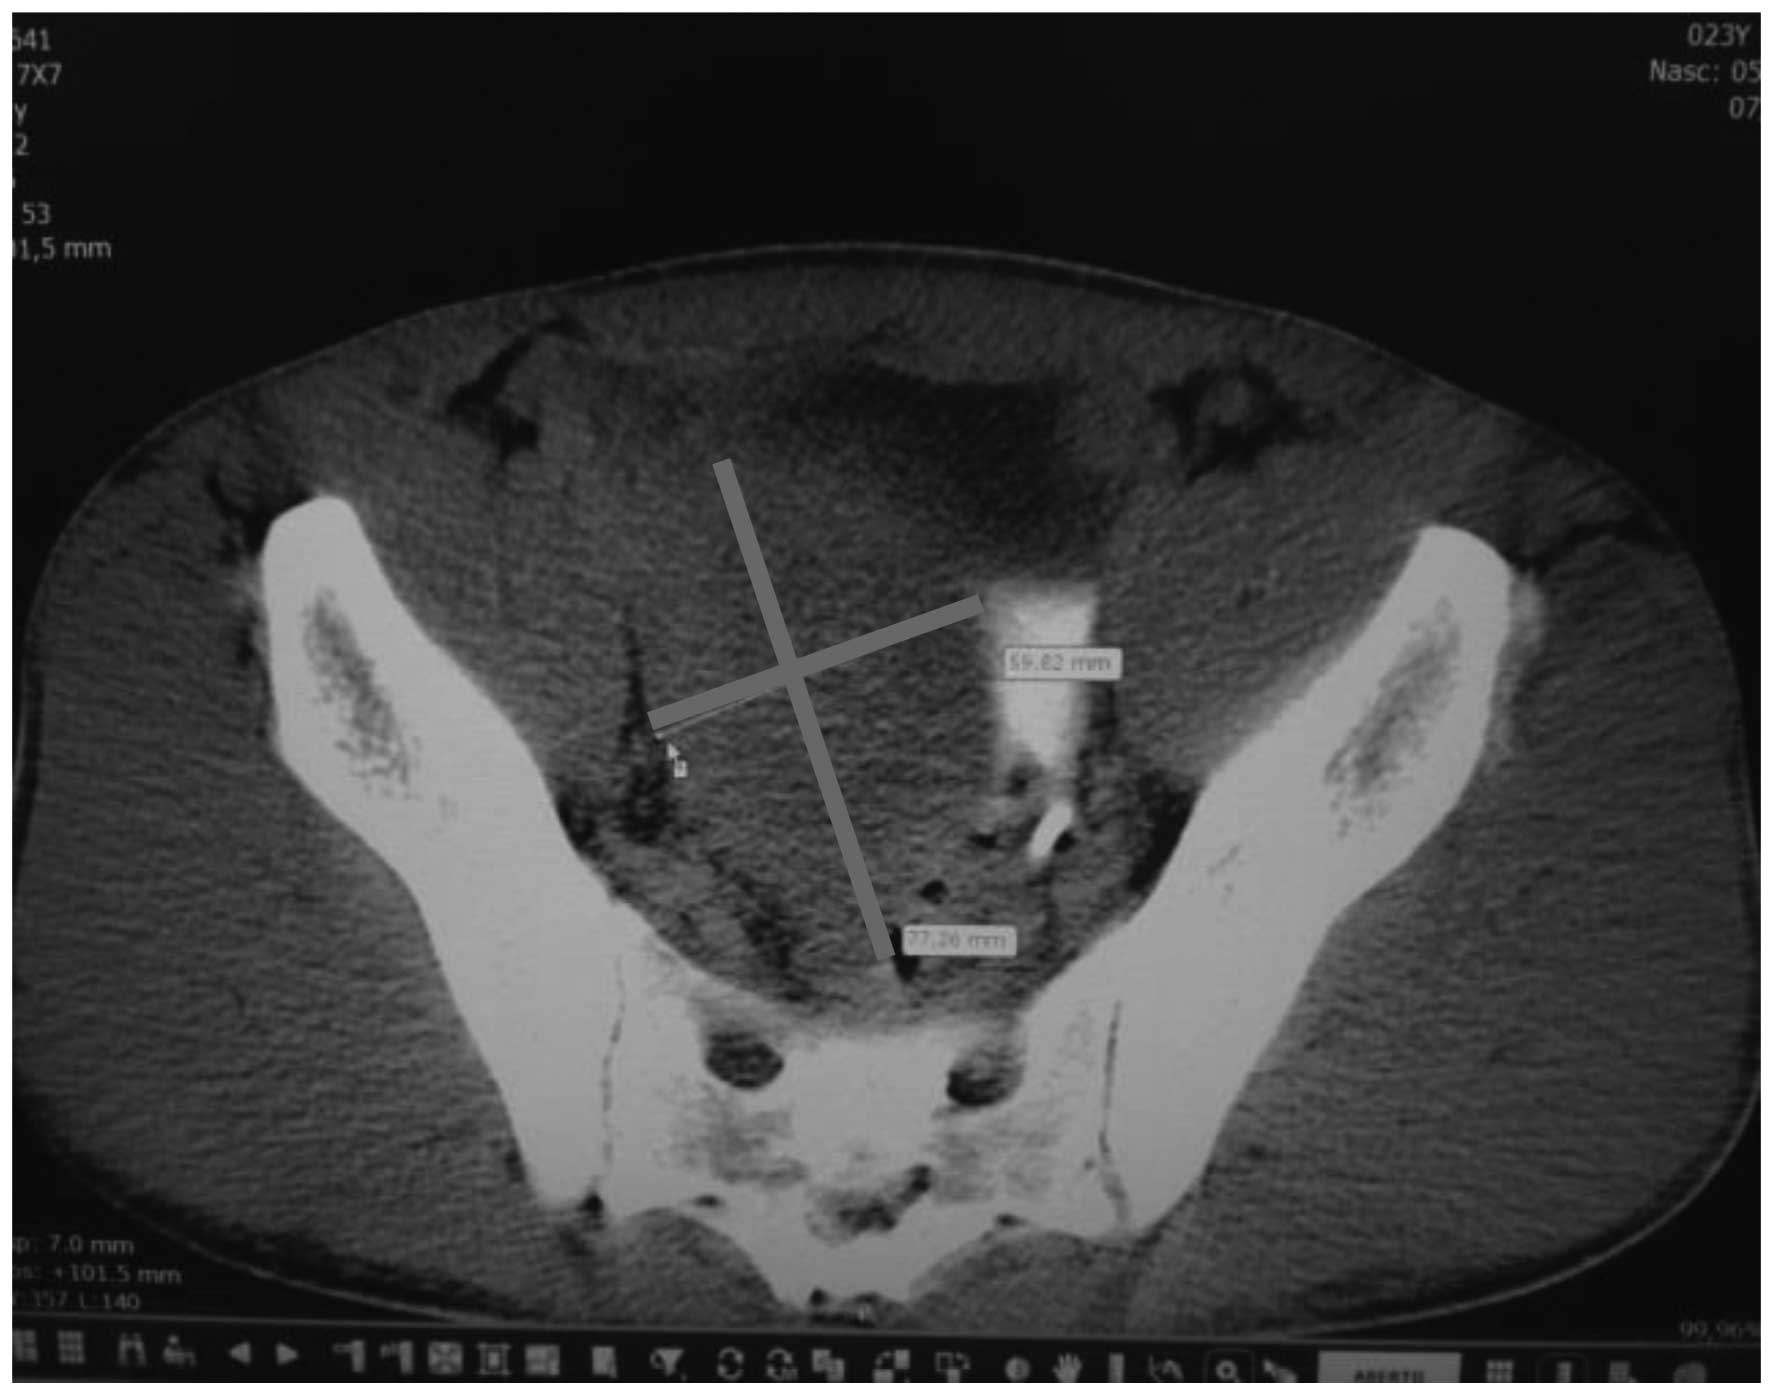

Computed tomography (CT) scans of the abdomen and pelvis revealed a heterogeneous, hypovascular pelvic mass measuring 7.6×6.8 cm (Fig. 1). The mass was located posteriorly and superiorly to the bladder, with thickening of the rectum and a right large hydronephrosis (Fig. 2). Additionally, colonoscopy identified extrinsic compression into the rectum. The differential diagnosis was of a lymphoproliferative lesion or retroperitoneal sarcoma. However, subsequent ultrasound-guided biopsy and histopathological analysis of the pelvic mass indicated a morphology compatible with a high-grade malignant neoplasm. It was characterized by groups of small cells featuring large and hyperchromatic nuclei with scant cytoplasm, arranged in the desmoplastic stroma. Immunohistochemical analysis of this sample revealed positivity for cytokeratin (monoclonal mouse anti-human; clone, AE1/AE3) and desmin (monoclonal mouse anti-human; clone, D33), and negativity for S100 protein (polyclonal rabbit anti-S-100), CD45 (leucocyte common antigen; monoclonal mouse anti-human; clone, 2D1), myogenin (monoclonal mouse anti-myogenin; clone, F5D), chromogranin (polyclonal rabbit anti-human) and WT-1 (Wilms' tumor suppressor gene 1; monoclonal mouse anti-human; clone, 6FH2; all purchased from Dako North America, Inc., Carpinteria, CA, USA). The CD45 negativity excluded a diagnosis of lymphoma. These morphological and immunohistochemical findings indicated a diagnosis of DSRCT (World Health Organization classification, 2013) (7).

During a laparotomy, right hydronephrosis was observed that was caused by a large tumor involving the cecum, terminal ileum and right ureter. Implantation of the tumor was identified in the right colon, liver and pelvic cavity, with involvement of the rectum. Consequently, a resection of the terminal ileum, cecum, right colon, distal segment of ureter, sigmoid colon and middle rectum was performed. In addition, a right, left and pelvic peritoniectomy was performed. Intestinal reconstruction was re-established with an ileo-transverse anastomosis associated with a left colostomy, implantation of a proximal urether into the bladder and insertion of a double-J catheter (Figs. 3 and 4). The post-operative follow-up was uneventful, however, deep vein thrombosis occurred in the right lower limb 20 days after surgery.